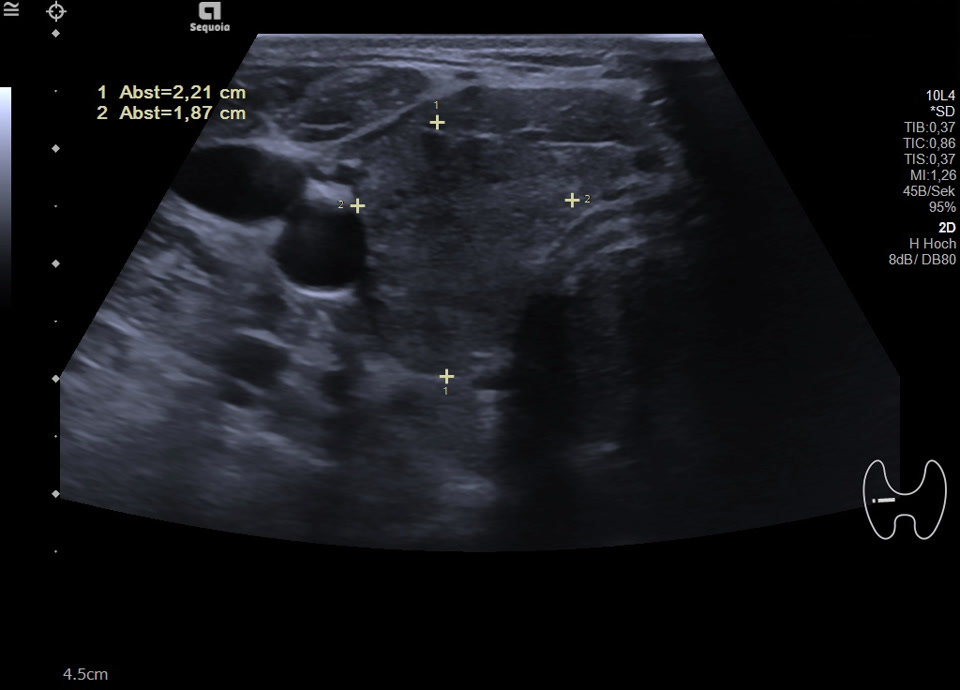

36-jähriger Patient mit Tremor, Tachykardie, Exophthalmus und Gewichtsverlust. Sonographisch stellt sich die Schilddrüse beidseits mit echoarmer inhomogener Parenchymstruktur dar. Gesamtvolumen 20,5 ml. Farbdopplersonographisch hypervaskularisiert. Laborbefunde: basales TSH erniedrigt, T3/fT4 erhöht, TRAK positiv. Befundkonstellation vereinbar mit M. Basedow. Unter Therapie mit Thiamazol und Propranolol beschwerdefrei. Bei Verlaufskontrolle zwei Jahre später sonographisch echoreiches minimal inhomogenes Parenchym bei normalem Volumen (15 ml).